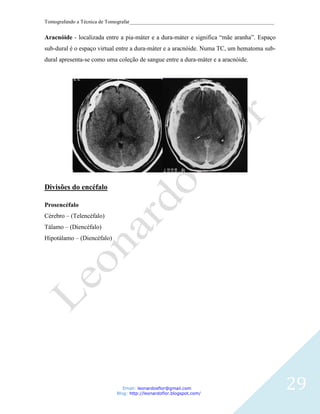

Aracnóide - localizada entre a pia-máter e a dura-máter e significa “mãe aranha”. Espaço

sub-dural é o espaço virtual entre a dura-máter e a aracnóide. Numa TC, um hematoma sub-

dural apresenta-se como uma coleção de sangue entre a dura-máter e a aracnóide.

Divisões do encéfalo

Prosencéfalo

Cérebro – (Telencéfalo)

Tálamo – (Diencéfalo)

Hipotálamo – (Diencéfalo)